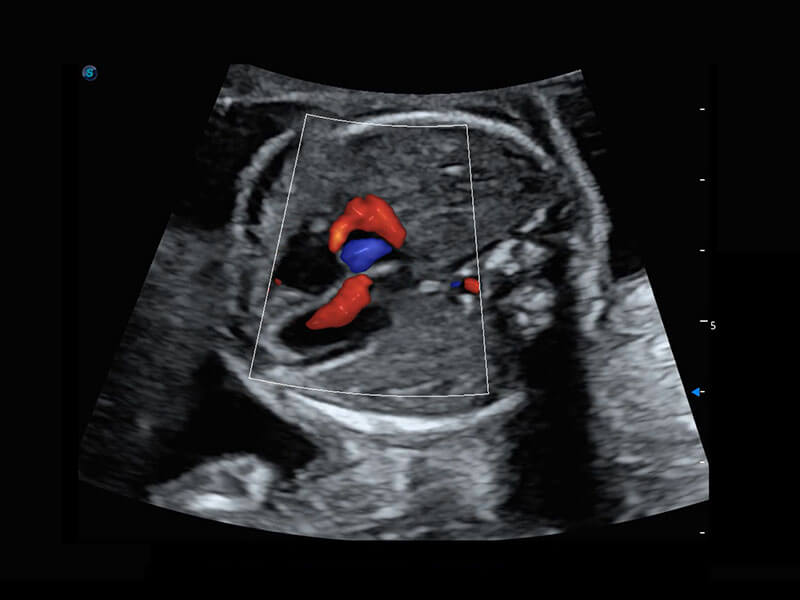

胎儿体循环

P60搭载一系列胎儿心脏成像技术,实现精细的胎儿心脏评估。

右室双出口

胎心容积成像